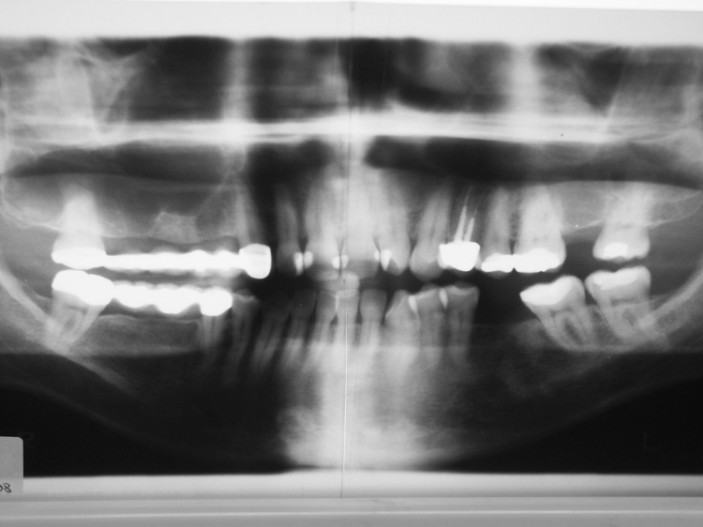

Am 5.12.2000 stellte sich die zu dem Zeitpunkt 30-jährige Patientin erstmalig in unserer Praxis vor. Aufgrund von starken Zahnbehandlungsängsten vermied die Patientin trotz gelegentlich starker Zahnschmerzen seit über zehn Jahren den Besuch beim Zahnarzt. Die mittlerweile auch im sichtbaren Bereich entstandenen Zahnschäden ließen aber letztendlich den Leidensdruck der Patientin so stark ansteigen, dass sie sich an unsere Praxis mit der Bitte einer Zahnbehandlung unter Einsatz zahnärztlicher Hypnose wandte. Beim ersten Termin wurde das Aufklärungsgespräch über Hypnose durchgeführt und die zu erwartenden Investitionen besprochen. Um den zu erwartenden Sanierungsbedarf einiger-maßen abschätzen zu können, wurde ein Orthopantomogramm (OPG) an­gefertigt (Abb. 1). Nach genauer Ex­ploration der die Angst auslösenden Faktoren erfolgte eine positive Zielorientierung hin zu einer entspannten Zahnbehandlung.